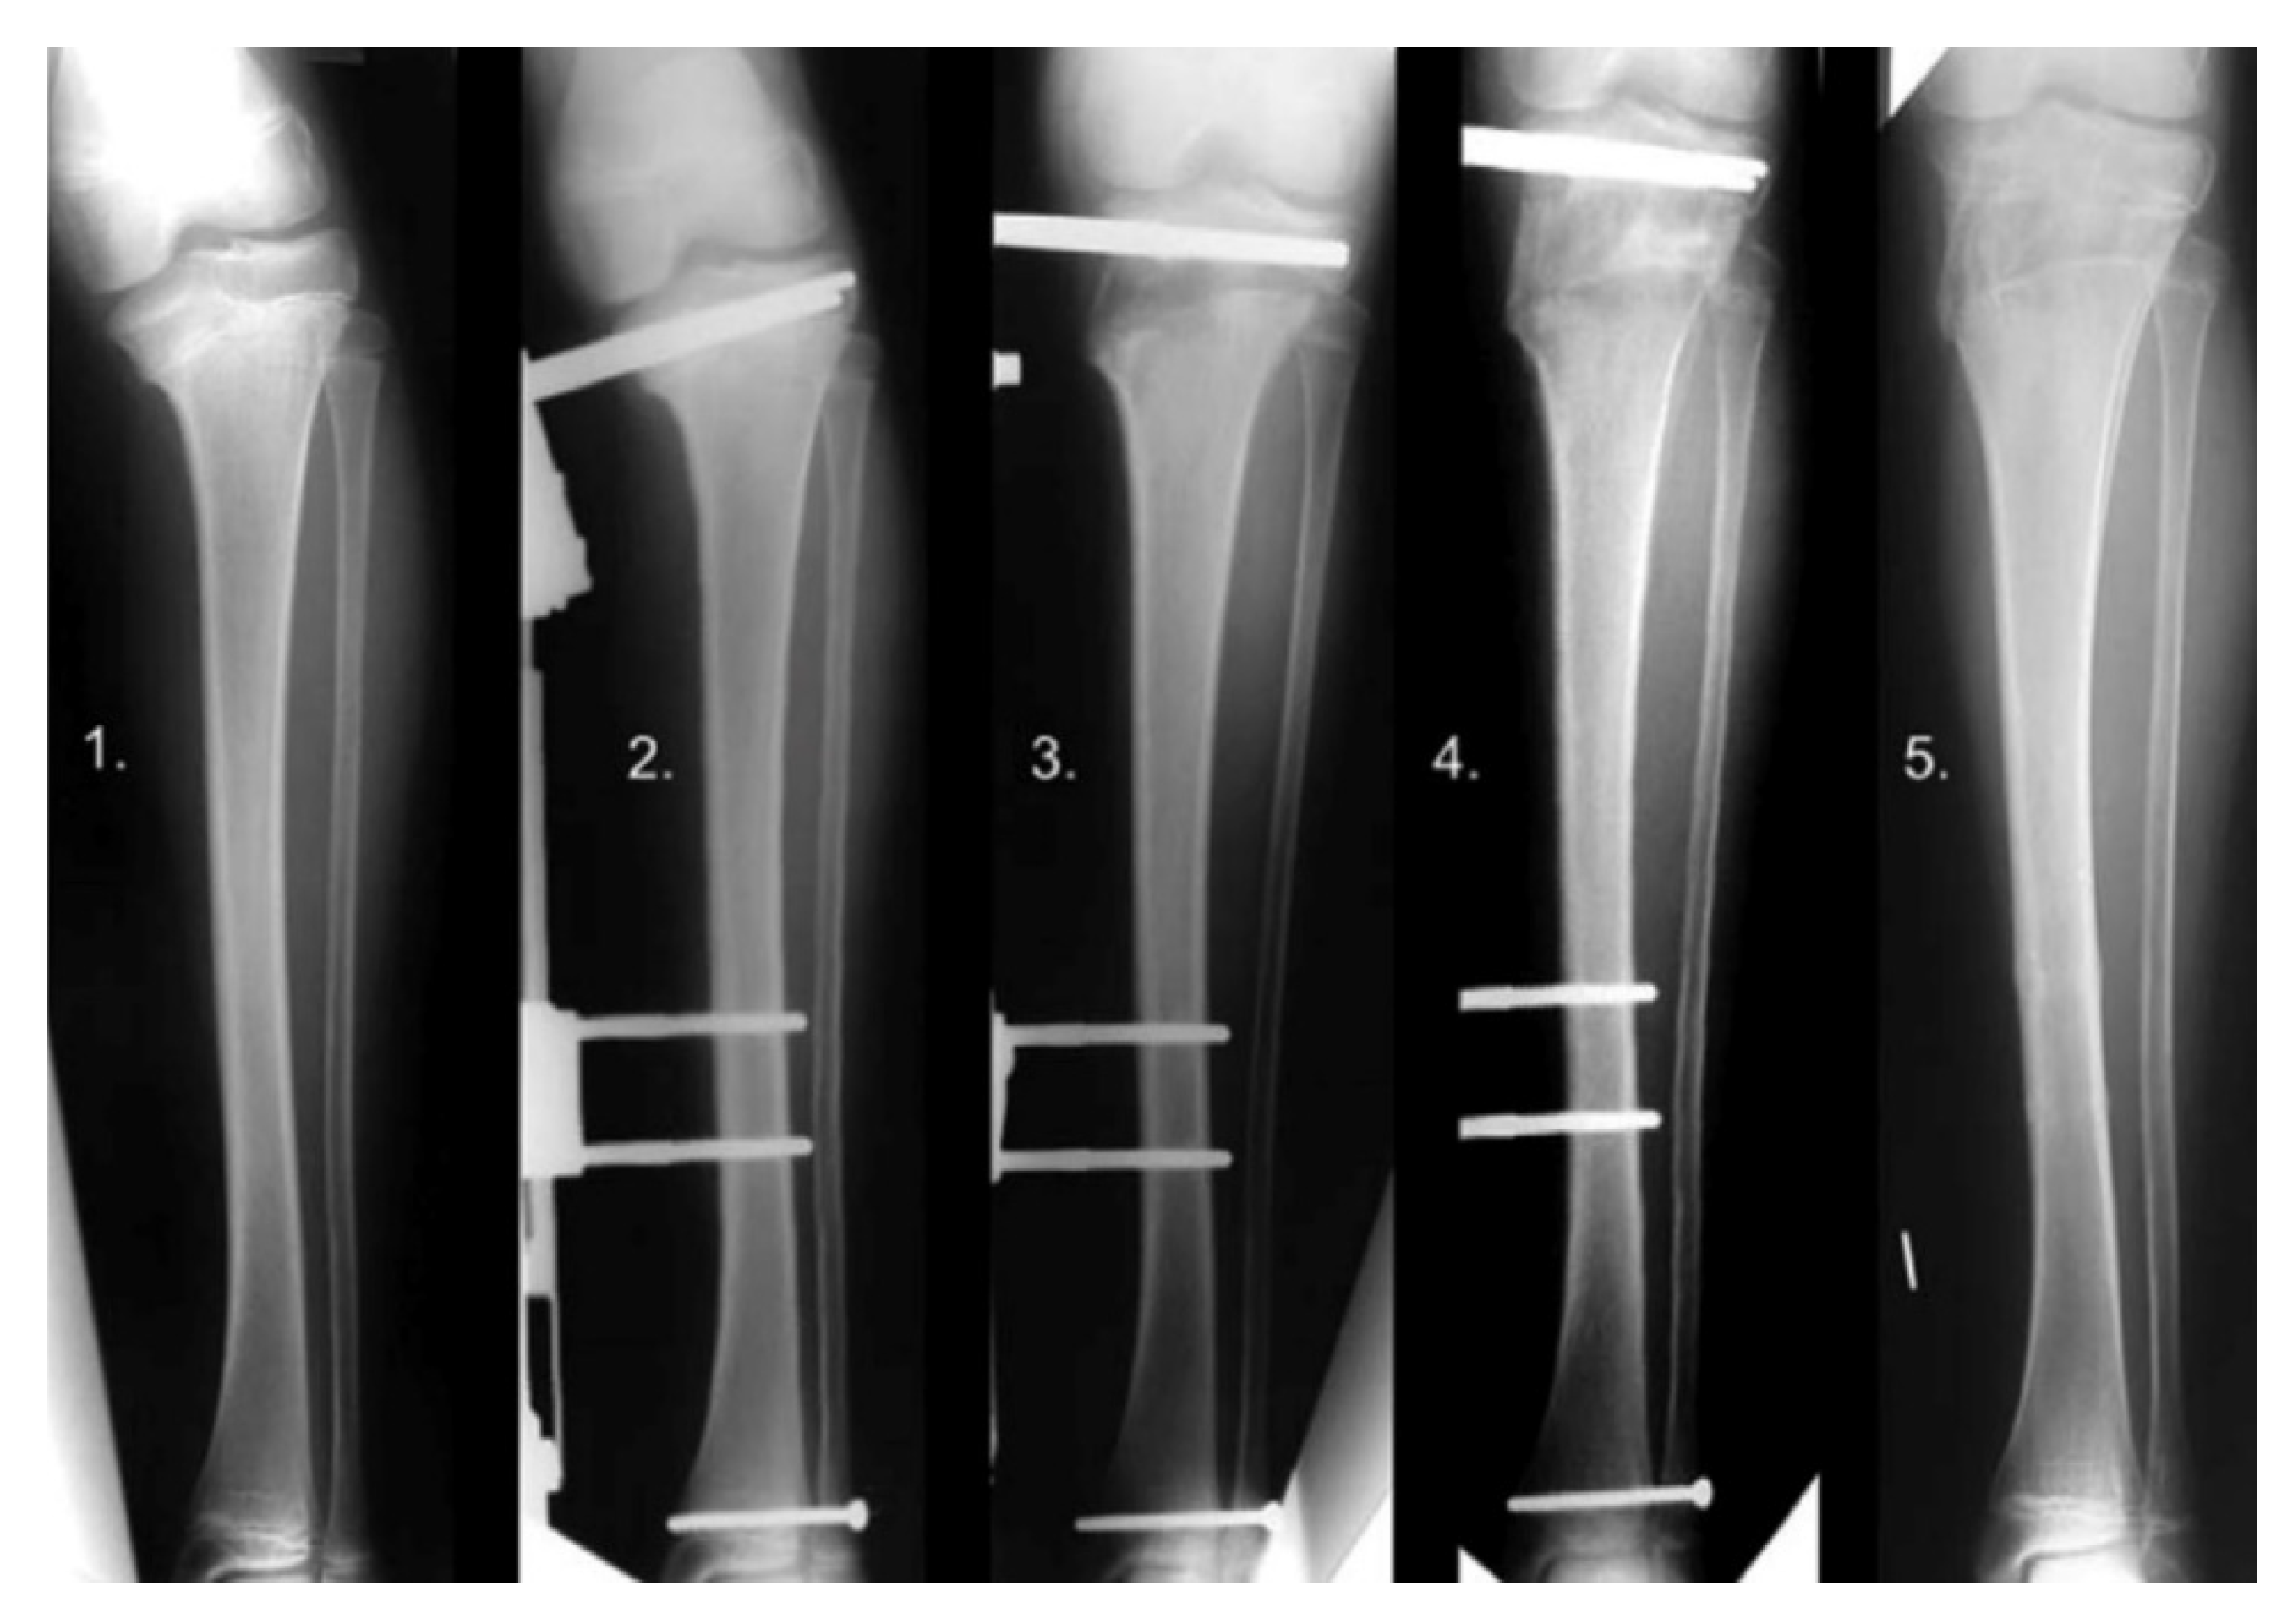

12. Physeal Arrest Resection

13. Osteotomies with Acute Correction

14. Hemi-Plateau Elevation Osteotomy

15. Combined Osteotomies

16. Epiphysiodesis

17. Gradual Correction with External Fixation